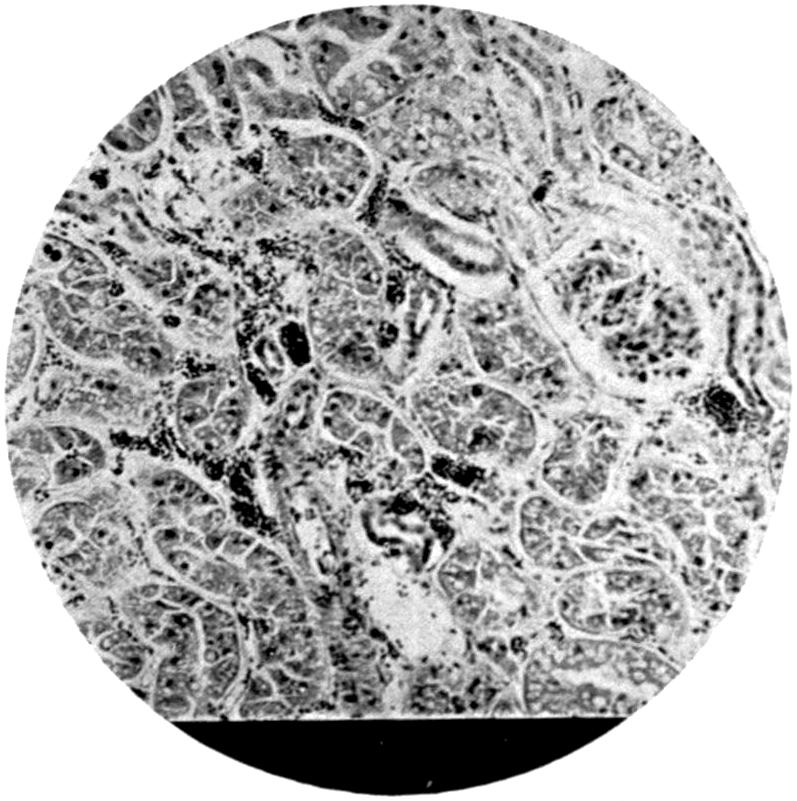

LIST OF PLATES

FACING

PAGE

Plate IV. 276